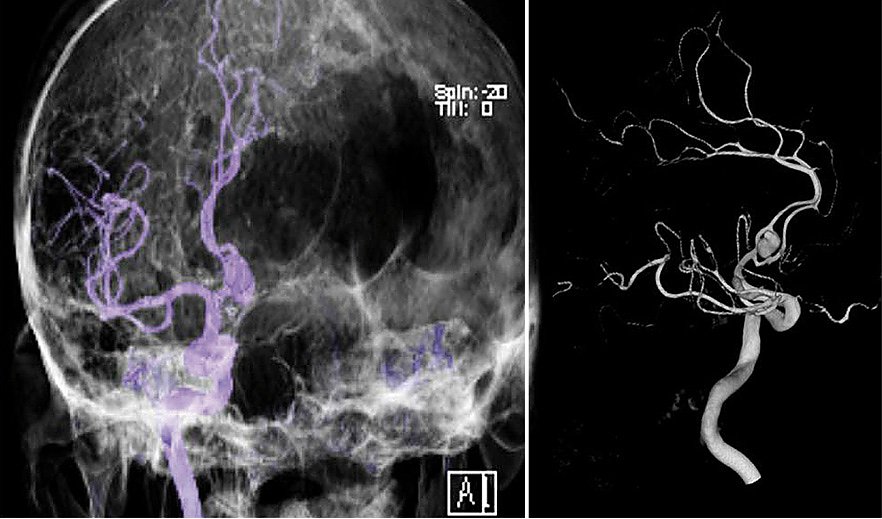

Bei der Subtraktionsangiografie wird eine Arterie im Ellbogen, Handgelenk oder (am häufigsten) in der Leiste punktiert. Über diese Punktion wird ein sehr flexibler Draht eingebracht und über diesen dann ein Katheter. Mit dieser Technik können sehr viele, auch sehr kleine, Gefäße, beispielsweise im Kopf, aber auch tumorversorgende Gefäße dargestellt werden. Mit der Angiografie können verstopfte Gefäße aufgeweitet werden, andere Gefäße, die beispielsweise bösartige Tumoren versorgen, dauerhaft verschlossen werden. Auch Gefäßerkrankungen wie die Verschlusskrankheit kann durch die Angiografie behandelt werden und Gefäßaussackungen (Aneurysmata) verschlossen werden. Wir führen als eine der sehr komplexen Interventionen die transarterielle Chemoembolisation durch, bei der der gefäßverschließende „Kleber“ mit einem Chemotherapeutikum verbunden ist, dass dann direkt in den (Leber)tumor eingebracht wird und dort auch verbleibt. Um eine Angiografie durchführen zu können, muss die Nierenfunktion über eine Blutentnahme geklärt werden, ebenso die Funktion der Schilddrüse. Außerdem ist es wichtig, die Blutgerinnungswerte zu kennen. Selbstverständlich wird jeder Patient ausführlich vor einer solchen Untersuchung individuell ärztlich aufgeklärt, weil hierbei auch Komplikationen auftreten können, wie Gefäßverletzungen, Blutergüsse und ungewollte Gefäßverschlüsse durch Verstopfungen (Thrombembolie), was je nach Untersuchungsbereich auch zu einem Hirnschlag (Apoplex) führen kann. Trotzdem ist die Angiografie aus der modernen Radiologie insbesondere bei interventionellen verfahren nicht wegzudenken. Als einzige Klinik in Nordthüringen haben wir eine Angiografie, die technisch auf exzellentem Niveau ist, weil wir zeitgleich aus zwei Röhren Bilder erstellen können, was Untersuchungszeit und Komplikationsrisiken deutlich verringert (biplane Subtraktionsangiografie).

Momentaufnahme während der Angiografie (Foto: SHK) Momentaufnahme während der Angiografie (Foto: SHK)